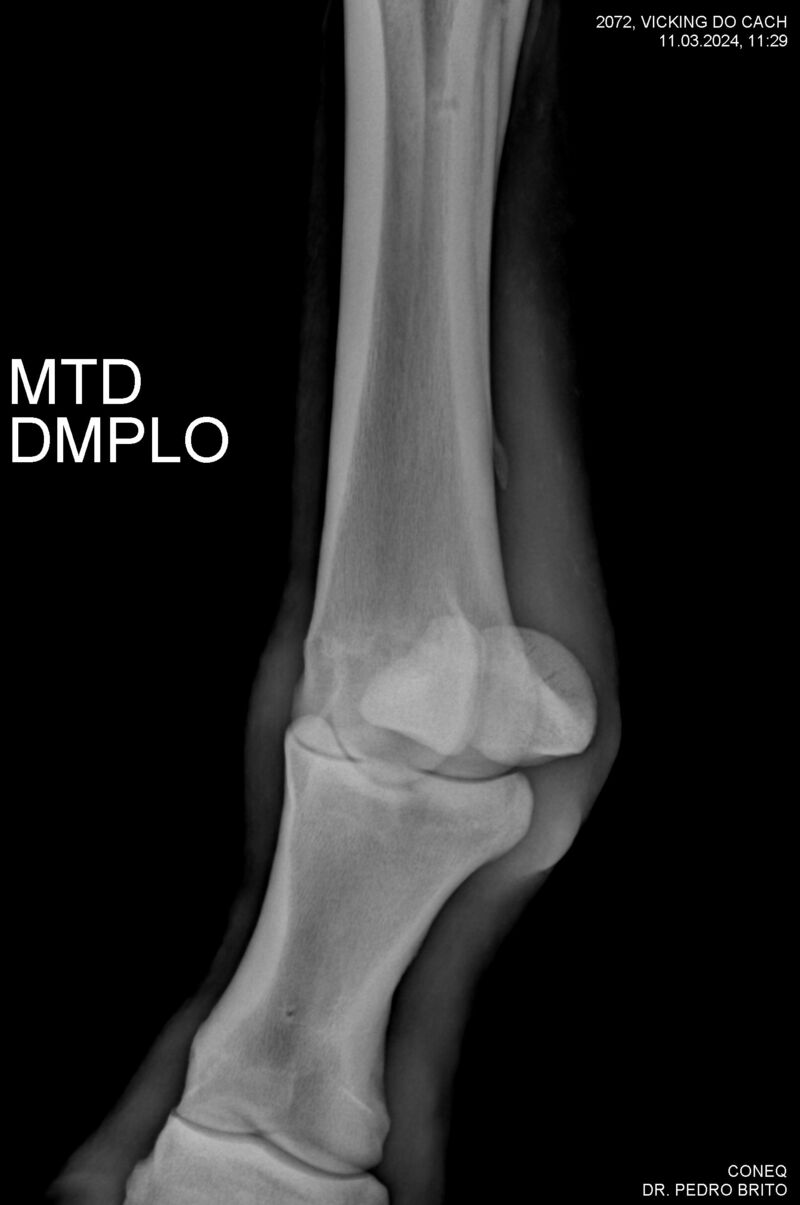

VIKING DO CACH